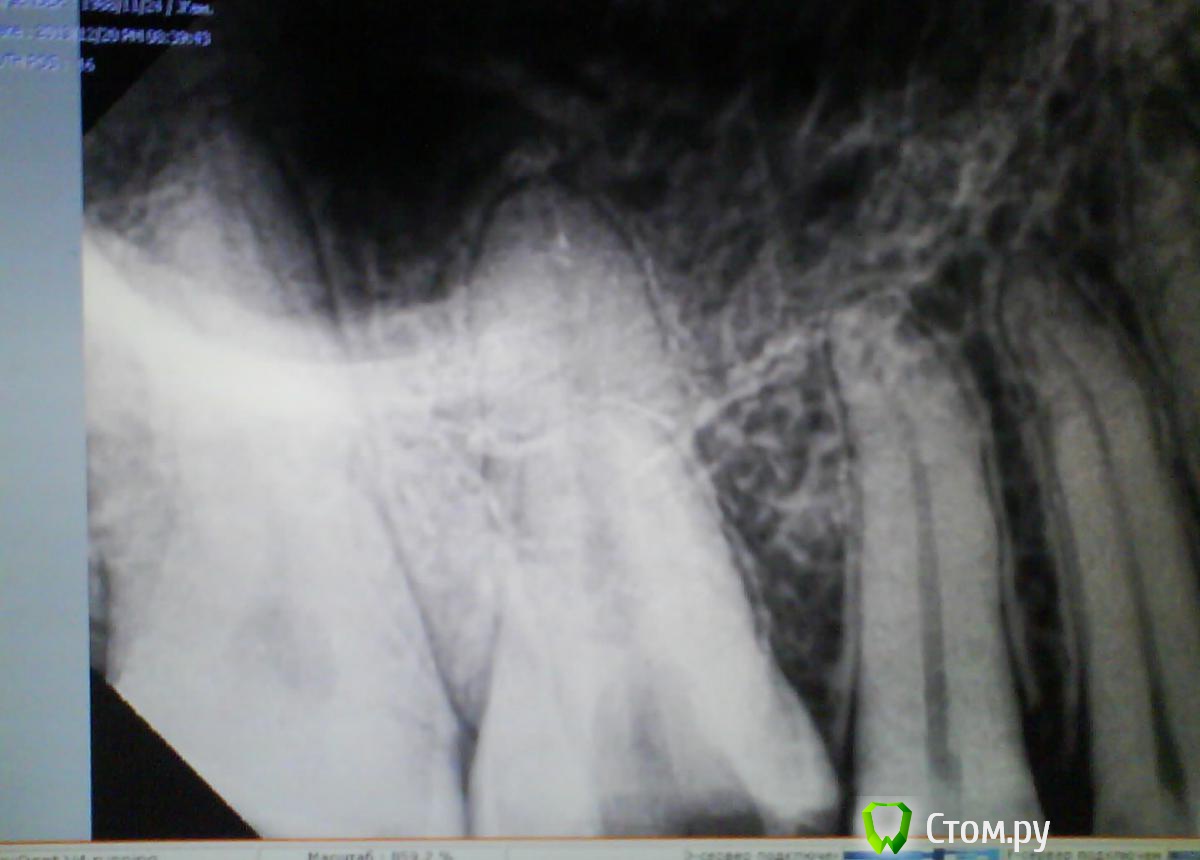

Scathach Опубликовано 20 декабря, 2013 Автор Поделиться Опубликовано 20 декабря, 2013 Дорогие докторы, выкладываю снимки. Прошу прощения за качество, пришлось шпионски снимать на телефон) Другой стоматолог сказала, что ничего криминального не во рту, ни на снимке не наблюдает.Высказала варианты: 1) корень зуба заходит в гайморову пазуху2) есть-таки маааленький хронический периодонтит3) разыгрался травматический периодонтит из-за кривой пломбы За три дня в открытом состоянии вроде стало чуточку полегче, но в целом картина прежняя - пока зубом я не жую, он остро не болит, но много раз в день возникают странные ощущения в десне, её как бы распирает немного изнутри и зуб кажется "больше" других, потом это пропадает. При постукивании зуб не болит вообще, на горячее не реагирует. Боль только когда сильно смыкаются зубы при жевании. И зуб, и десна по ощущениям (языком) намного теплее, чем "соседи". Десна при нажатии болит точно над зубом (высоко, там где уже чувствуется кость и начинается ткань щеки). Есть что-то типа маленькой болезненной штучки в этом месте, если пощупать пальцем, но никакого открытого свища и пр. нет. Ссылка на комментарий

red_butler Опубликовано 21 декабря, 2013 Поделиться Опубликовано 21 декабря, 2013 Ничего страшного не увидел, как можно скорее долечивайте зуб. Зуб оставлять открытым нельзя, происходит массивное обсеменение корневых каналов микроорганизмами из слюны. Найдите стоматолога эндодонтиста владеющего современными протоколами лечения корневых каналов Ссылка на комментарий